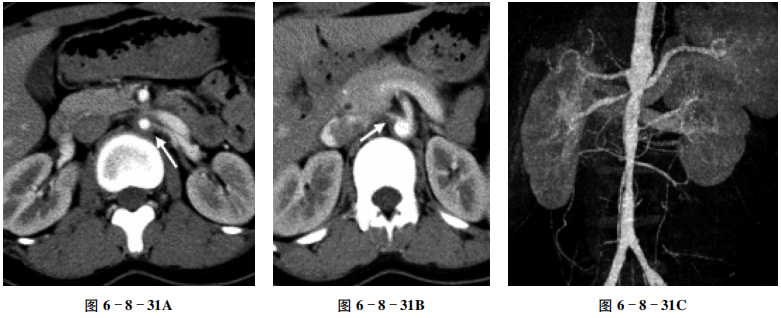

【CT征象】

增强扫描皮质期双肾动脉起始处(箭头)及腹主动脉管壁弥漫性增厚,管腔明显狭窄,腹主动脉管壁增厚呈“同心圆”改变(图6-8-31A、B);VR示左肾动脉全程纤细狭窄,右肾动脉起始处管腔明显狭窄,腹主动脉粗细不均(图6-8-31C、D)。